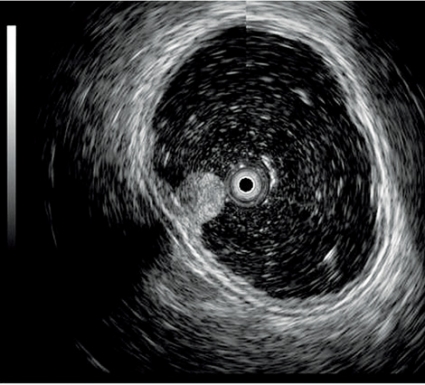

Det första instrumentet tillverkades 1980 och bestod av en enkel mekanisk ultraljudstransduktor kopplad till ett vanligt gastroskop. I dag finns två typer av elektroniska ekoendoskop: det radiella och det linjära. Det radiella instrumentet återger en ultraljudsbild i 360° som är vinkelrät mot instrumentet, medan det linjära instrumentet ger en bild som är parallell med instrumentets axel. Bara det linjära instrumentet möjliggör vägledning av en nål för finnålsaspiration, biopsi eller injektion genom att nålen kan följas i realtid vid införandet i vävnaderna (Figur 1).